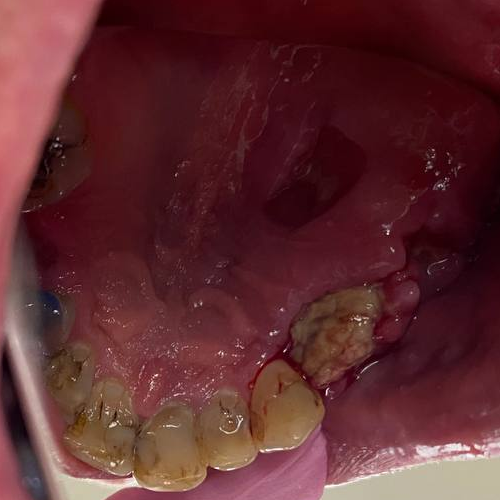

It'sGeorgy Опубликовано 28 мая, 2021 Поделиться Опубликовано 28 мая, 2021 Здравствуйте. 21.05.21: Язычносмещенный разрез, удаление оставленного корня 2.4, удаление 2.6 и 3.8. Имплантаты 2.4, 2.5. Пошел сделал снимок: Не понравился дистальный наклон 2.5, пошел перекручивать. Пока крутил-вертел торк с 25 упал до пальцевого. Принял решение установки коротких формиков, ССТ вестибулярно и ушивания наглухо. Сегодня пациент пришел на осмотр к другому доктору, а там вот такая печалька: Какие ошибки предполагаю сам: 1. Слишком толстый трансп, ушивание которого вызвало перенатяжение 2. Медиальный шов, который держит трансп совсем хиленький и, на самом деле, мало что держит. И главный вопрос: что делать? Оставлять и надеяться, что что-то приживется или полностью убирать? Ссылка на комментарий

АнтонТЛТ Опубликовано 28 мая, 2021 Поделиться Опубликовано 28 мая, 2021 Пусть пока побудет, нижние слои хоть немного да прилипли. Рот не санирован, гигиена перед операцией не сделана. Какой смысл в свободном трансплантате был? Ссылка на комментарий

Карен Аванесов Опубликовано 29 мая, 2021 Поделиться Опубликовано 29 мая, 2021 Ждать, полоскать пассивно или лизобакт, а на будущее, при таком шикарной ретромолярной области, не трогать болезненное небо. 11 часов назад, АнтонТЛТ сказал: Пусть пока побудет, нижние слои хоть немного да прилипли. Рот не санирован, гигиена перед операцией не сделана. Какой смысл в свободном трансплантате был? Доктор получил опыт и выводы сделает. 1 Ссылка на комментарий

АнтонТЛТ Опубликовано 30 мая, 2021 Поделиться Опубликовано 30 мая, 2021 Если так хочется по высоте добавить мягких тканей, то лучше на питающей ножке трансплантат (vip-ct). А тут получился толстый трансплантат, который не успел нормально прорасти сосудами, да ещё слишком близко к линии разреза. Мобилизация вестибулярного лоскута была? Если нет, то может швами ещё передавил его питание. Пациент курит? 1 Ссылка на комментарий

Irouil Опубликовано 30 мая, 2021 Поделиться Опубликовано 30 мая, 2021 ИМХО изначально дизайн разреза и план трансплантации мало совместимы. Покрывной (и питающий) лоскут получился очень длинным, он себя с горем пополам кровью обеспечивает, а уж стать источником и для графта - это тяжело. Если планируете графтить - лучше сразу разрез стараться посередине гребня размещать, а если не планировали, а получилось как получилось - действительно лучше как советует @АнтонТЛТ , брать самый надёжный вариант 1 Ссылка на комментарий